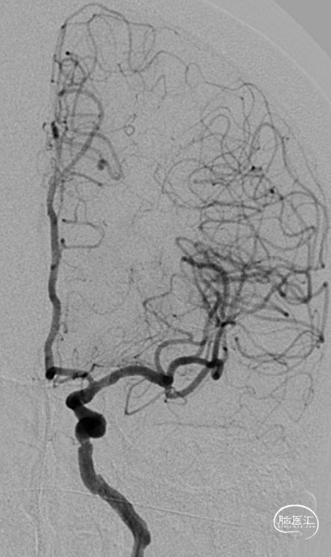

术前影像

脑血管造影(主动脉弓造影及后循环)

右侧颈动脉造影

左侧颈动脉造影

左侧颈内动脉重建(左侧狭窄及扩张较右侧更甚)

扩张后再次复查造影示支架打开及贴壁较前明显改善

标准正侧位造影未见远端血管栓塞

稀释造影提示支架贴壁可,狭窄改善